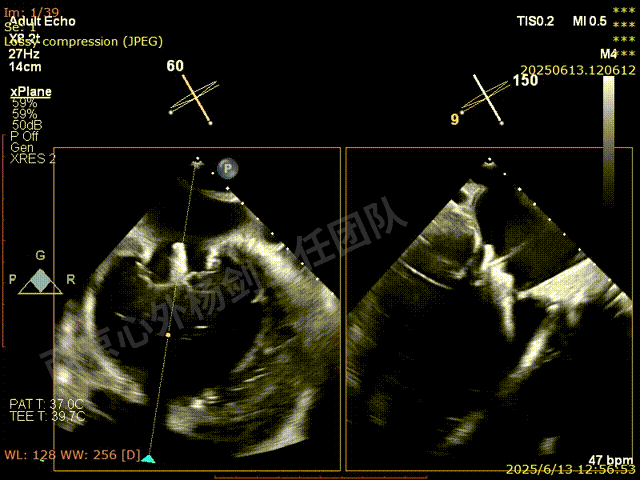

二尖瓣后叶栓系严重,前叶相对错位,反流束沿2区分布广泛,2偏3区处存在反流。

反流宽度至少23mm,因影像调整困难,考虑实际反流更宽。